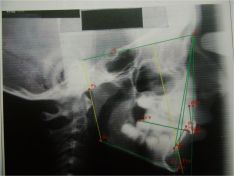

Caso clinico interessante. la ragazza presenta un evidente morso profondo grave deviazione della linea mediana e scarso spazio eruttivo per 13 e 23.

Decido di seguire il caso sviluppando l'arcata superiore grazie alla enorme versatilita del sistema Damon. Propongo anche l'uso di un elastoposizionatore T4braces per migliorare la performans del sistema.

Ottima collaborazione, risultato piacevole.